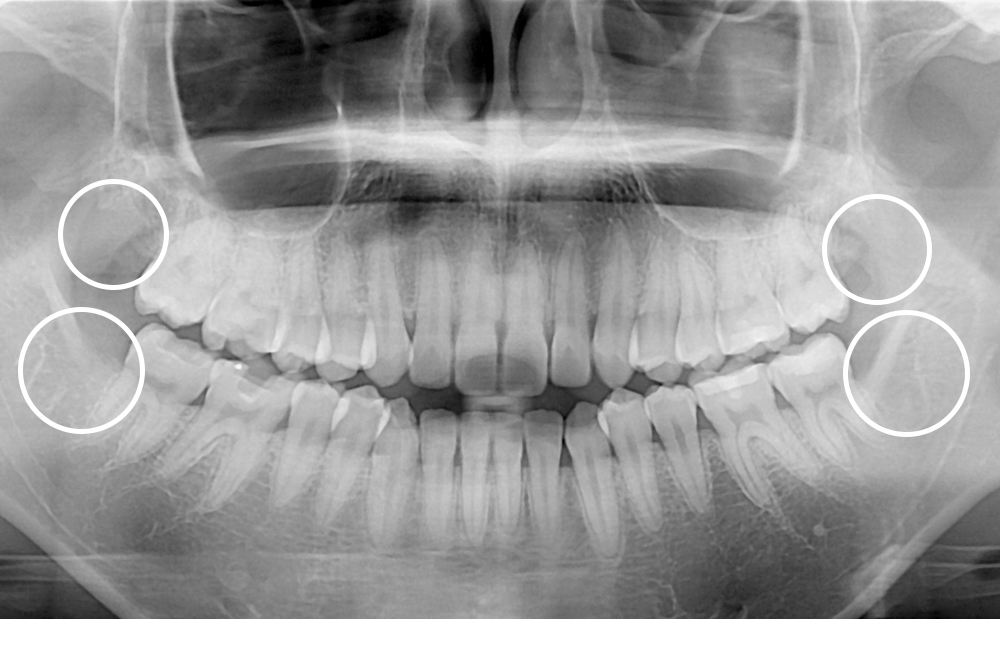

치료후 : 2021-03-08

세종치과는 구강악안면외과학 박사이신 원장님이 발치하는 치과입니다.